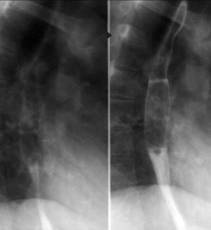

Portiunea terminala a esofagului este īngustata axial cu contururi netede. Esofagul supraiacent este dilatat uneori foarte mult. Umplerea se face de jos īn sus. Exista lichid de staza. Undele peristaltice sunt vii, frecvente dar ineficiente. Staza esofagiana dureaza 3-4 ore. Cardia se destinde la un moment dat producāndu-se evacuarea īntregului continut esofagian (legea totul sau nimic). Aceasta particularitate a evacuarii esofagului diferentiaza cardiospasmul de achalazie.

Cardiospasmul

Achalazie